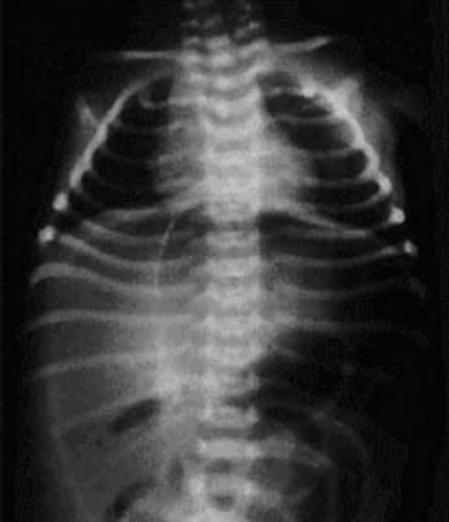

Es importante comprobar la presencia de otros signos radiológicos que pueden indicar una evolución tórpida con presencia de un asa intestinal fija, extensión de la neumatosis a la circulación venosa portal o la presencia de neumoperitoneo (Fig. 2.24.3).

Debe hacerse con infecciones sistémicas o intestinales, íleo paralítico u otros cuadros obstructivos abdominales, trombosis vascular y, sobre todo, con la perforación intestinal aislada del RNP de muy bajo peso, que durante mucho tiempo no se diferenciaba de la ECN y que recientemente ha quedado definida como una entidad separada. Los defectos congénitos de la muscular intestinal, la isquemia intestinal, los agentes infecciosos y medicaciones, como la indometacina y la dexametasona, parecen relacionarse con este proceso. La presencia de neumoperitoneo sin imagen de neumatosis, ni otras alteraciones aparentes, apoya el diagnóstico (Fig. 2.24.3). La lesión suele ser única a nivel del íleon terminal, siendo normal el resto del intestino.